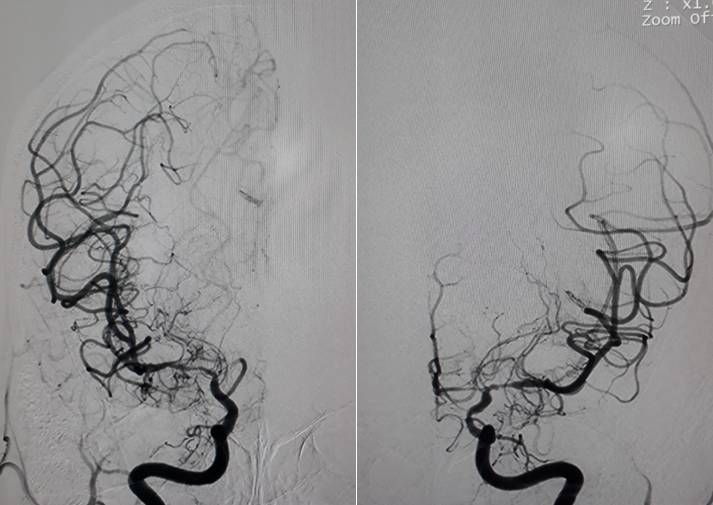

Hình chụp DSA động mạch cảnh trong phải và trái: hẹp khít động mạch não giữa hai bên đoạn M1.

Hình chụp DSA động mạch cảnh trong trái: hẹp khít động mạch cảnh trong trái đoạn mấu giường.

Hình chụp DSA động mạch đốt sống: bàng hệ cho hệ tuần hoàn trước từ hệ thống tuần hoàn sau

Bệnh Moya Moya là bệnh lý mạch máu hẹp tại gốc một số động mạch lớn trong sọ thuộc tuần hoàn trước (thuộc động mạch cảnh trong). Quá trình hẹp dần dần nên cơ thể thích nghi bằng các tuần hoàn bàng hệ bù cho vùng thiếu hụt tuần hoàn. Tuần hoàn bàng hệ phát triển tại chỗ hẹp bằng rất nhiều mạch máu nhỏ và yếu, dễ hình thành các phình mạch nhỏ và vỡ gây chảy máu não. Nếu tuần hoàn bàng hệ một lúc nào đó không đủ cấp máu cho não sẽ gây nên nhồi máu não tái đi tái lại. Trên chụp mạch, các mạch nhỏ tại chỗ hẹp tạo nên hình “những làn khói tỏa” (puff of smoke). Bệnh lấy tên một bác sĩ người Nhật là người đầu tiên mô tả về bệnh này trong y văn.